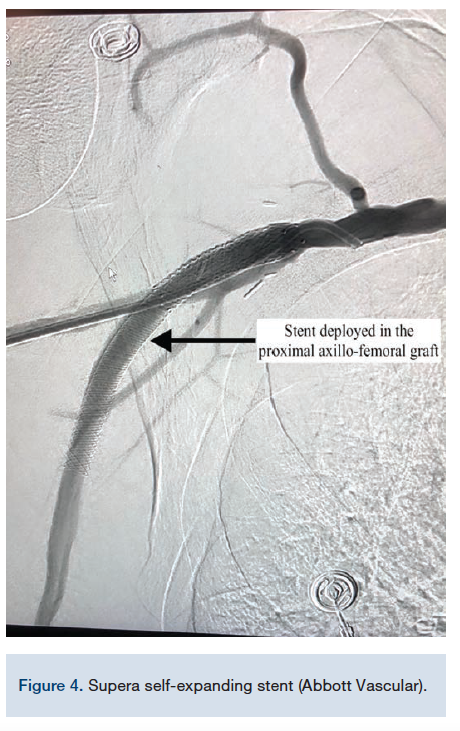

The radial artery was accessed using palpation and another 6 Fr sheath was placed. Selective angiography of the subclavian was obtained, which showed flush occlusion of the axillary bypass graft (Figure 2). A left internal mammary artery (LIMA) catheter was used via the transradial approach and an .014-inch wire was successful in crossing the ostial occlusion of the graft with the pedal guidewire as a marker. Through transradial access, 6.0 mm balloon angioplasty was performed successfully of the entire length of the bypass graft and a Supera self-expanding stent (Abbott Vascular) was deployed with excellent results (Figures 3-4). For more precise deployment, a self-expanding Innova stent (Boston Scientific) was deployed in the ostial part of the graft (Figures 3-4). The right SFA was treated via transpedal access with a combination of atherectomy, mechanical thrombectomy, and stenting. Finally, a tPA infusion was administered overnight through the transradial access (with the tip of the infusion catheter placed in the proximal axillary graft) (angiographic results, Figures 5A-C). To complete this complex procedure, <1 gray (Gy) of radiation was required, significantly less than a level that would cause concern for acute radiation side effects.